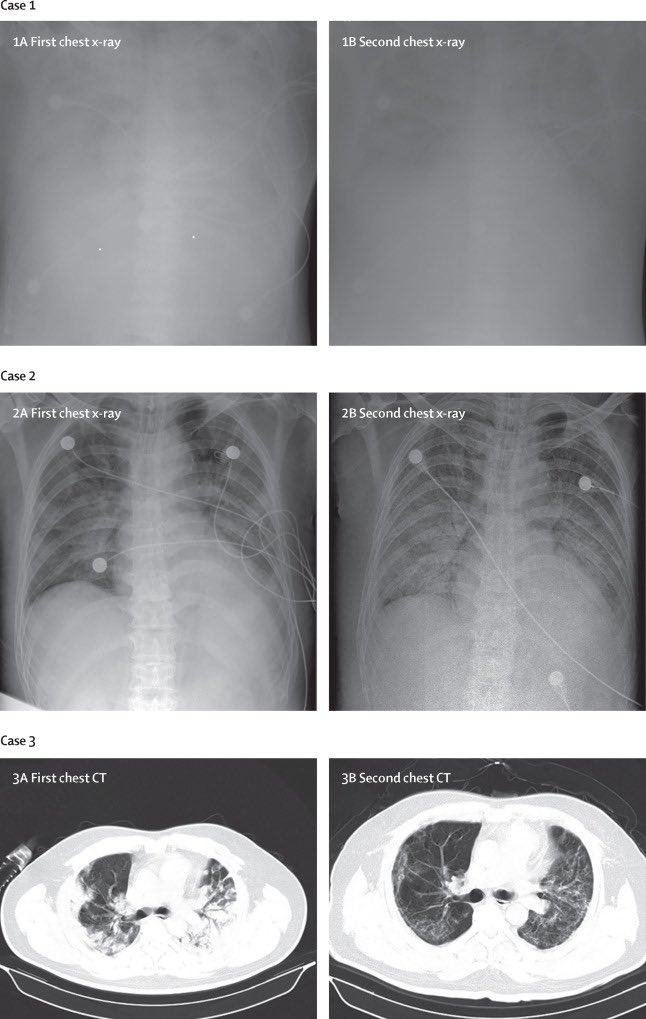

١-متلازمة الضائقة التنفسية الحادة(ARDS)

*بمعنى انه الرئة تمتلىء بالسوائل فلا تستطيع التنفس وهو امر مشابه جدا لما حدث في الانفلونزا الأسبانية